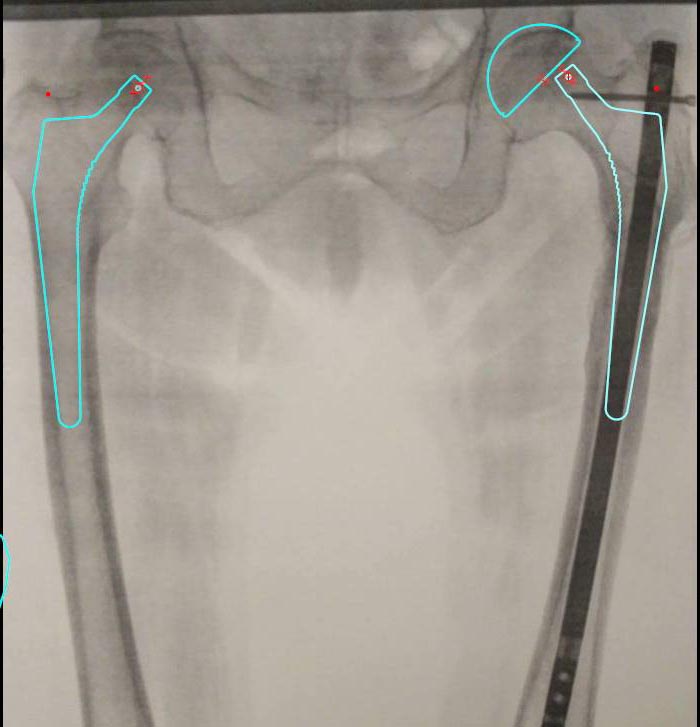

Тут не очень ясно виден сустав. Заодно бы и на второй посмотреть. Может статься, не такой уж там в суставе прямо ужас-ужас. И с нормальной осью ходила бы и без эндопротезов.

Михаил, не видно толком на этом снимке сустав. И на второй бы посмотреть. Если у нее до травмы были жалобы на суставы, и уже были мысли про эндопротезирование - нет вопросов. Если проблемы сейчас обусловлены деформацией - ее устранение их решит.

Михаил, обсуждаем в рамках имеющейся информации. Второй снимок показал, что сустав не разрушен. И что, раз пациентке 70+, ей все равно надо его поменять? Если не коррекция деформации, то что?

Михаил, эта версия основывалась на "явных признаках коксартроза", и это основание устранено последующим снимком.

Да и на последующем эти признаки есть.

Михаил, второй сустав не лучше выглядит. Надо тогда уж и его.

признаки есть, было бы странно, если бы их не было. Но сустав вполне себе ничего.

Да, откуда боли, когда мы не видим ничего? Пустяковая 30-градусная варусноя деформация не в счет, да? Ах, опять эта томительная неизвестность!

"Изменения в суставе" даже не привели еще к сужению суставной щели, и обычны для такого возраста, и готов поспорить, что до травмы она не стояла в очередь на эндопротезирование. То есть болезненные проявления обусловлены не артрозом, а недавней посттравматической внесуставной деформацией. И мучать пациентку - это как раз делать избыточную операцию по ампутации вполне годного проксимального отдела бедра. Которая в условиях подвертельной деформации еще и окажется не самой простой.